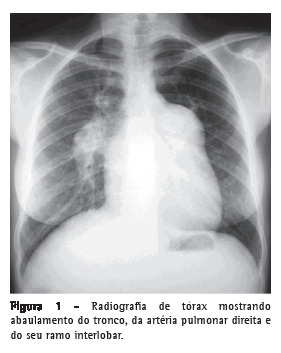

A ultrassonografia de abdome revelava espessamento ecogênico periportal central e periférico moderado, espessamento da parede da vesícula biliar, com sinais de hipertensão portal (veia porta = 13 mm e veia esplênica = 10 mm) e detecção de veia paraumbilical com 11 mm como via de circulação colateral, compatíveis com esquistossomose hepatoesplênica. O diâmetro longitudinal do baço era de 117 mm. A endoscopia digestiva alta revelava varizes esofagianas de pequeno calibre na primeira avaliação. As sorologias para hepatitis B surface antigen (HBsAg), antibody to hepatitis B surface antigen (anti-HBs), antibody to hepatitis B core antigen (anti-HBc) e antibody to hepatitis C virus (anti-HCV) foram negativas. A radiografia de tórax apresentava dilatação de artérias pulmonares e aumento das câmaras cardíacas direitas (Figura 1), confirmados pela TC de tórax (Figura 2). O eletrocardiograma apresentava sinais de sobrecarga de câmaras direitas. Ao ecocardiograma, havia aumento do átrio e do ventrículo direitos, com pressão sistólica de artéria pulmonar estimada em 145 mmHg, e dilatação aneurismática da artéria pulmonar (56 mm). Os resultados espirométricos foram os seguintes: VEF1 = 2,22 L (76%), CVF = 3,04 L (90%), VEF1/CVF = 73,03% e prova broncodilatadora negativa. A DTC6 foi de 153,6 m, e o teste foi interrompido aos 1,25 min por pré-síncope. A angiotomografia e a cintilografia pulmonar, realizadas previamente, evidenciavam dilatação aneurismática de artéria pulmonar, ausência de falhas de enchimento arterial pulmonar e baixa probabilidade para embolia pulmonar. O cateterismo cardíaco direito demonstrava pressão sistólica de artéria pulmonar de 140 mmHg, pressão média da artéria pulmonar de 88 mmHg, índice cardíaco de 3,0 L  min−1  m−2 e resistência vascular pulmonar de 23,0 Woods. A prova de vasorreatividade pulmonar com óxido nítrico foi negativa.

Dados de centros especializados em atendimento de pacientes portadores de HP no Brasil sugerem que a esquistossomose seja a causa da doença em pelo menos 30% dos pacientes. (16) A apresentação clinica parece ser similar à da HAP idiopática, caracterizando-se por dispneia aos esforços, fraqueza, tosse, palpitação, dor torácica e hemoptise. (16) Habitualmente, a radiografia de tórax mostra dilatação do tronco da artéria pulmonar e cardiomegalia devido ao aumento do ventrículo direito. (17,18)